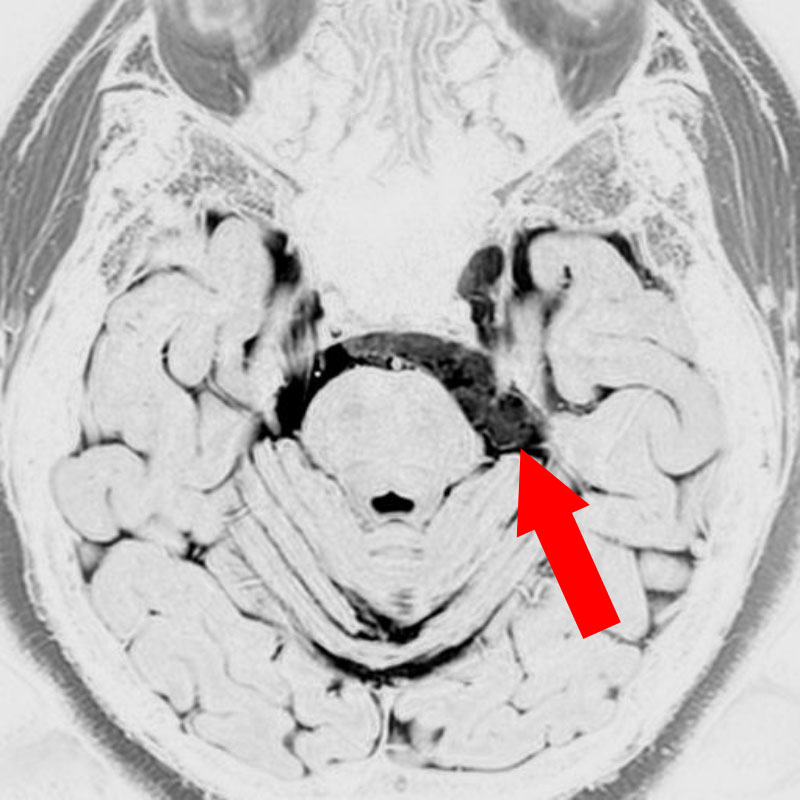

567

'24年9月

40代

小脳血管芽腫

頭蓋内腫瘍摘出術

No.’24_69 手術前1

No.’24_69 摘出 前

No.’24_69  摘出 中

No.’24_69 摘出 後